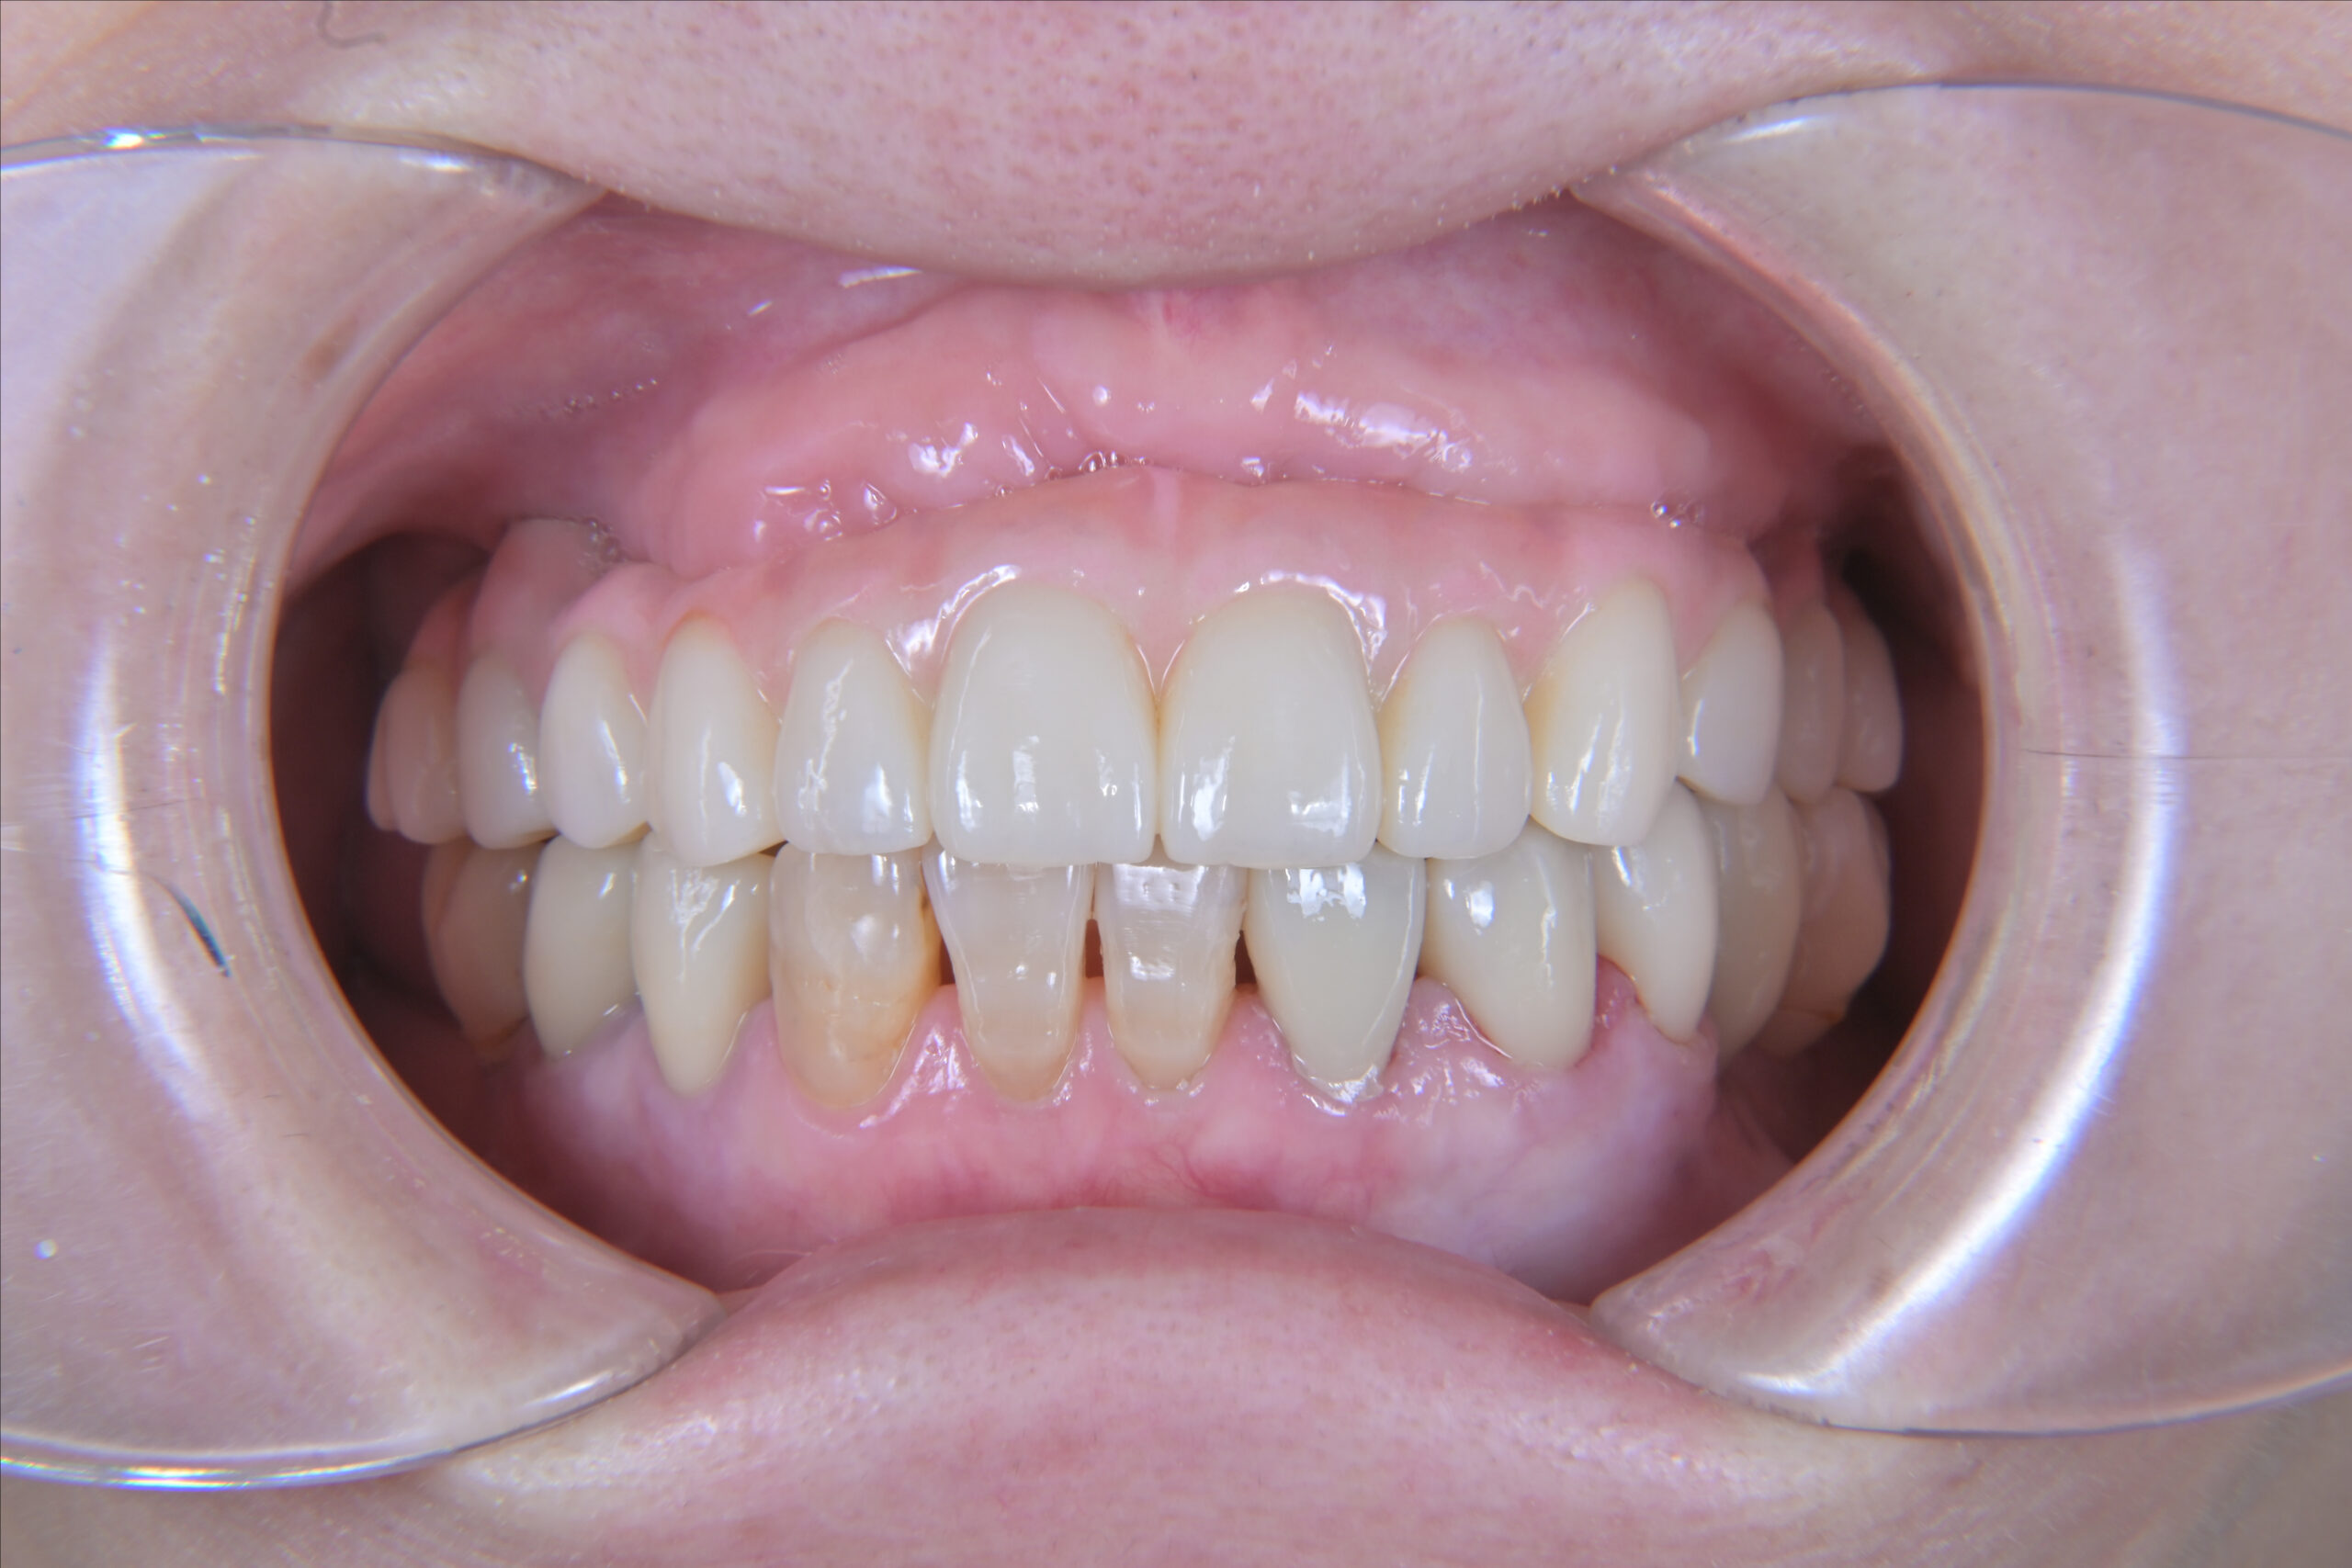

60代女性 AGC(全顎インプラント)

- AGC(全顎インプラント)治療

- 入れ歯を卒業したいと、全顎的なインプラント治療を決意されました。

- 特殊な「AGC構造」で作られるインプラントブリッジは、ネジも接着剤も使わず高精度の嵌合で固定されます。この患者様は6本で連結されており、簡単には外れませんが、専用器具で着脱可能です。丸洗いできるため衛生的で、将来的に介護が必要な場合も対応しやすいなどの特徴があります。